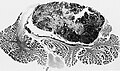

Classic medulloblastoma H&E stain. | |

- Classic medulloblastoma (~85% of all medulloblastomas).

Classic variant

- Densely packed embryonal cells.

- Mitosis / apoptosis present.

- Nodules of neurocytic differentiation without internodular reticulin.

- Rarely spongioblastic pattern (ribboning).